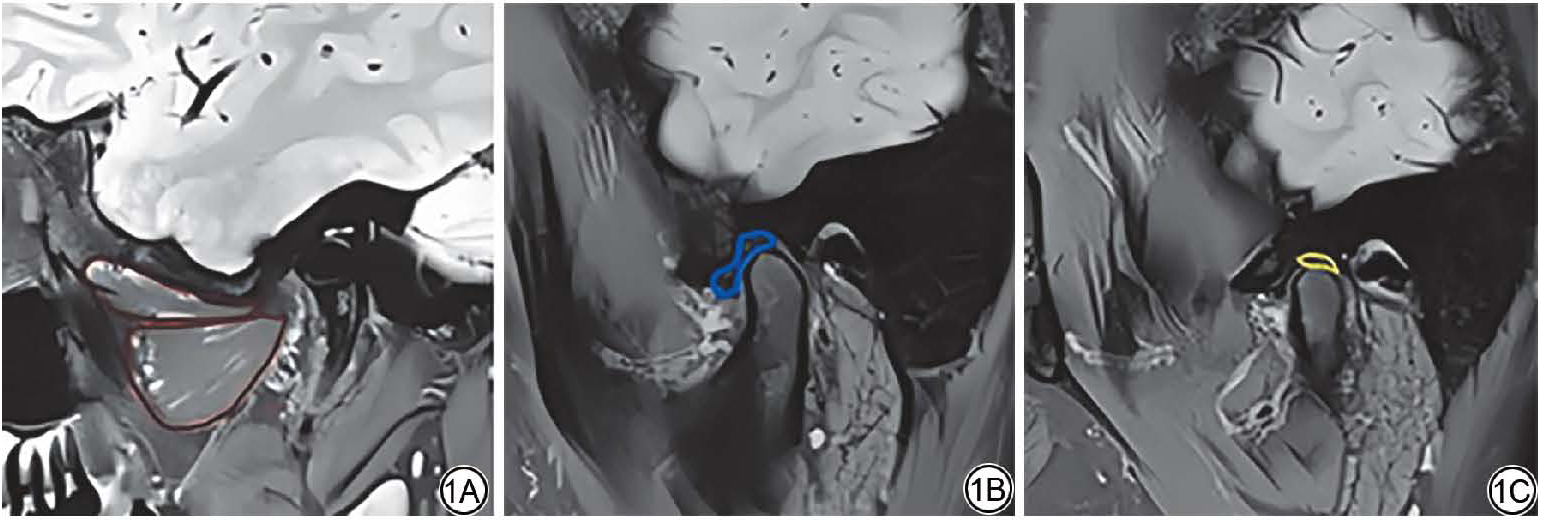

本研究基于质子密度加权像(proton density weighted imaging, PDWI)序列借助ITK-SNAP图像处理软件对MRI影像数据进行人工分割。具体操作流程如下:首先将原始DICOM格式的图像数据导入软件,并在图像数据基础上,手动精准勾勒出目标解剖结构对应的感兴趣区域(region of interest, ROI)。所有ROI的绘制均在软件预设的标准化操作界面内完成,且由两名独立操作人员独立分割。两名操作人员分别为一名具有9年MRI判读经验的影像科医师与一名经过TMJ结构分割标准化培训的影像医学研究生。在正式分割前,两名操作人员已完成10例预实验分割,其组内相关系数(intra-class correlation coefficient, ICC)达0.85,表明具有良好一致性。正式分割后通过ICC评估两名操作人员分割结果的一致性,采用双向随机效应模型、绝对一致性定义计算ROI体积的ICC值。并计算Dice相似系数(Dice similarity coefficient, DSC)来评估ROI空间重叠程度。DSC<0.7或ICC<0.75时由第三方影像科主任医师进行仲裁分割,仲裁分割结果将与两名操作者中一致性较高的一方重新计算ICC,以确保最终分割结果的可靠性。最后再随机选取25例数据重复分割,再次计算ICC,结果得出翼外肌、关节盘及双板区ICC值分别为0.91、0.93和0.94,均超0.90,说明分割结果可靠性良好。此次研究中ROI区域主要包含三部分,分别为翼外肌、关节盘以及双板区(图1)。

图1  翼外肌(1A,红色)、关节盘(1B,蓝色)、双板区(1C,黄色)勾画示意图。

Fig. 1  Images segmentation of the lateral pterygoid muscle (1A, red), articular disc (1B, blue), and bilaminar zone (1C, yellow).